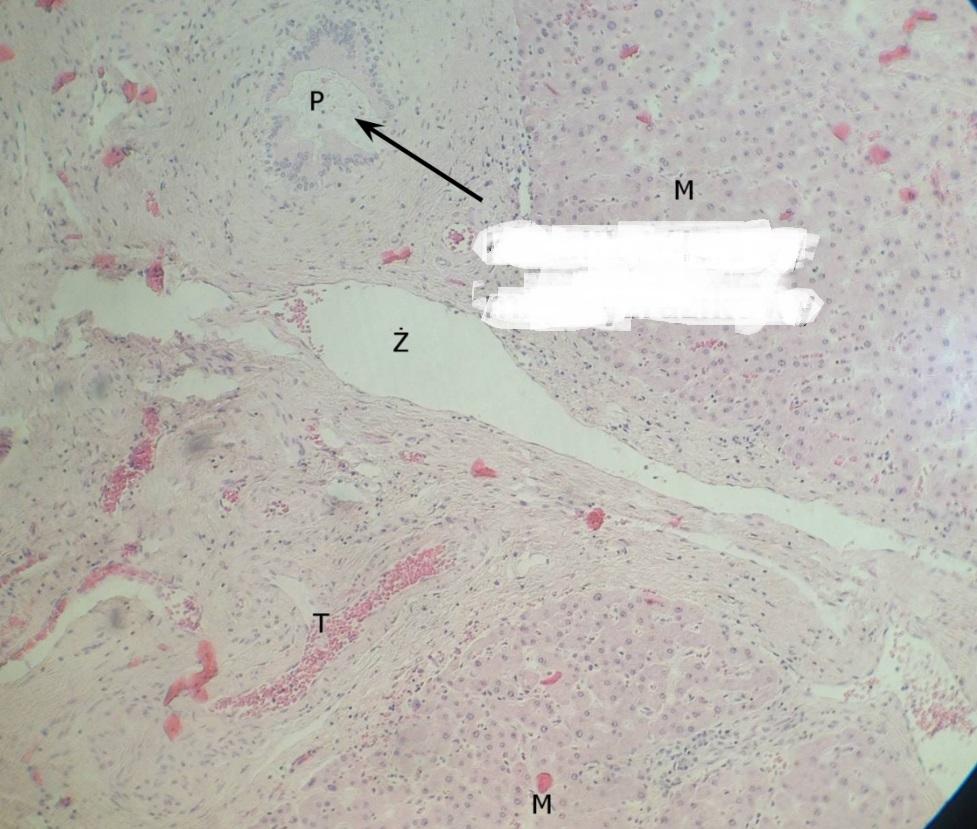

Pytanie 444

żyła międzyzrazikowa - największa z triady (wątroba świni, triada)

Pytanie 445

tętnica międzyzrazikowa - widać wyraźnie mięśniówkę (wątroba świni, triada)

Pytanie 446

kanalik żółciowy międzyzrazikowy - wygląda, jak pętla korali (wątroba świni, triada)